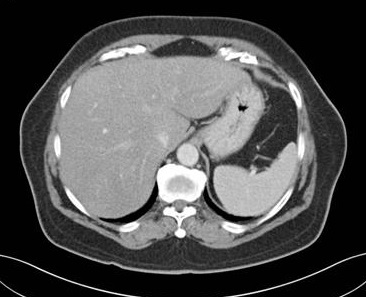

En cas steatose du foie la

densite du foie est moins dense 10UH que la rate |

Image TDM d'une steatose du

foie : Le foie est hypodensse que la rate . Gradient

normal sans injection foie/rate =10UH |